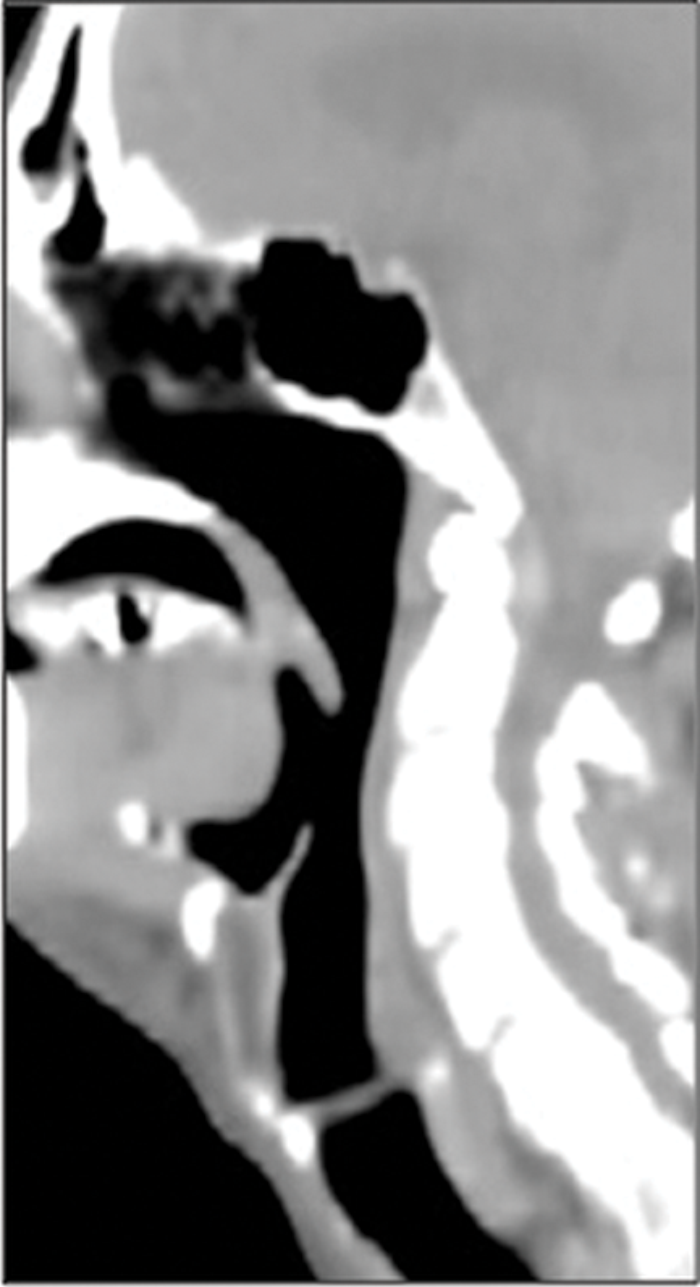

Figure 2: Patient with clinical suspicion of recurrent disease in the oro-pharynx. No recurrence was identified in clinical assessment, MR and on EUA and biopsy of suspicious areas. FDG PET-CT shows the recurrence in the wall of an ulcer crater in the base of tongue (arrow). A = FDG, B = CT, C = combined PET-CT.